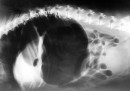

Avantaggiato fotografa animali, padroni, attrezzatura e ambienti all’interno di diversi ambulatori veterinari, con l’idea che «l’eccellenza clinica è al servizio dell’animale e l’animale è più uomo dell’uomo». Attraverso immagini di ambienti sterili, freddi e tecnologici, Avantaggiato sottolinea questa che lui definisce una anomalia: cliniche pulite e all’avanguardia messe al servizio degli animali. Con i suoi ritratti prova a personificare il “paziente”, per sottolineare ancora di più questo aspetto.